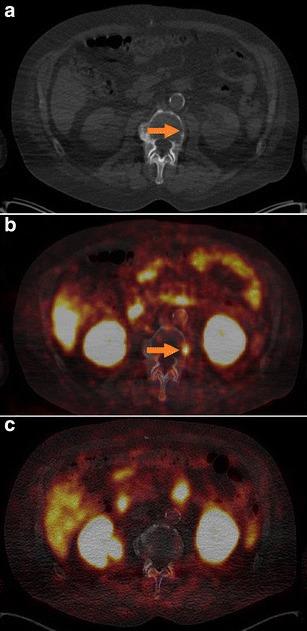

In 14 selected patients with PSA relapse of prostate cancer, [(18)F]DCFPyL PET/X-ray computed tomography (CT) was performed in addition to [(68)Ga]Ga-PSMA-HBED-CC PET/CT. A systematic comparison was carried out between results obtained with both tracers with regard to the number of detected PSMA-positive lesions, the standardized uptake value (SUV)max and the lesion to background ratios.

RESULTS

All suspicious lesions identified by [(68)Ga]Ga-PSMA-HBED-CC were also detected with [(18)F]DCFPyL. In three patients, additional lesions were observed using [(18)F]DCFPyL PET/CT. The mean SUVmax in the concordant [(18)F]DCFPyL PSMA-positive lesions was significantly higher as compared to [(68)Ga]Ga-PSMA-HBED-CC (14.5 vs. 12.2, p = 0.028, n = 15). The mean tumor to background ratios (n = 15) were significantly higher for [(18)F]DCFPyL compared to [(68)Ga]Ga-PSMA-HBED-CC using kidney, spleen, or parotid as reference organs (p = 0.006, p = 0.002, p = 0.008), but no significant differences were found using the liver (p = 0.167) or the mediastinum (p = 0.363) as reference organs.

CONCLUSION

[(18)F]DCFPyL PET/CT provided a high image quality and visualized small prostate lesions with excellent sensitivity. [(18)F]DCFPyL represents a highly promising alternative to [(68)Ga]Ga-PSMA-HBED-CC for PSMA-PET/CT imaging in relapsed prostate cancer.

在14例选定的前列腺癌PSA复发患者中,除了进行[(68)Ga]Ga-PSMA-HBED-CC PET/CT外,还进行了[(18)F]DCFPyL PET/X射线计算机断层扫描(CT)。对两种示踪剂获得的结果在检测到的PSMA阳性病变数量、标准化摄取值(SUV)最大值和病变与背景比值方面进行了系统比较。

结果

[(68)Ga]Ga-PSMA-HBED-CC识别出的所有可疑病变也能用[(18)F]DCFPyL检测到。在3例患者中,使用[(1)F]DCFPyL PET/CT观察到了额外的病变。与[(68)Ga]Ga-PSMA-HBED-CC相比,[(18)F]DCFPyL PSMA阳性病变中的平均SUV最大值显著更高(14.5对12.2,p = 0.028,n = 15)。以肾脏、脾脏或腮腺作为参考器官时,[(18)F]DCFPyL的平均肿瘤与背景比值(n = 15)显著高于[(68)Ga]Ga-PSMA-HBED-CC(p = 0.006,p = 0.002,p = 0.008),但以肝脏(p = 0.167)或纵隔(p = 0.363)作为参考器官时未发现显著差异。

结论

[(18)F]DCFPyL PET/CT提供了高质量的图像,并以优异的灵敏度显示了小的前列腺病变。对于复发前列腺癌的PSMA-PET/CT成像,[(18)F]DCFPyL是[(68)Ga]Ga-PSMA-HBED-CC极具前景的替代物。